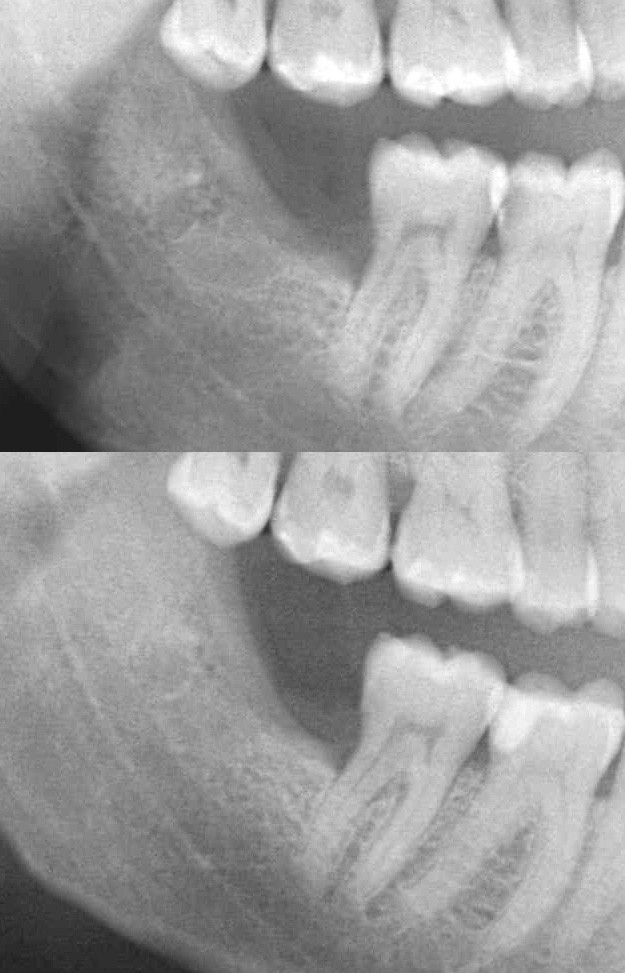

Figure 3

(a) An immediate postoperative dental panoramic tomography was obtained to be considered as a baseline image for this case study. (b) Radiographic image, obtained 50 days postoperatively showing enhancement of radiopacity in the third molar socket area.